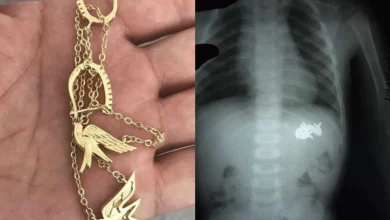

Қызылордада екі жасар баланың асқазанынан алтын білезік алынды

Қызылордада екі жасар анасының алтын білезігін жұтып қойған. Анасы бастапқыда бағалы әшекейдің жоғалғанын байқамаған екен. Алайда кейін тексеріс кезінде күдігі…